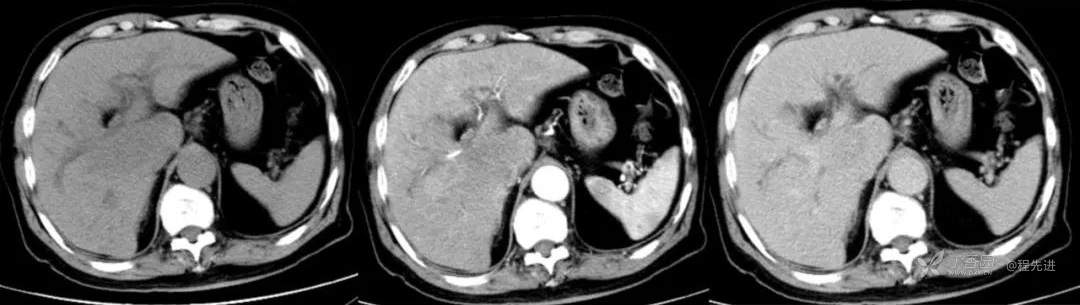

简要病史:因胸部不适入院,胸部CT示:肺部感染性病变;腹部CT示:肝门区占位性病变